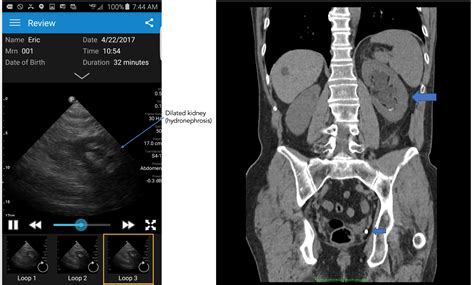

Ultrasound Imaging

Ultrasound is a preferred initial choice for specific populations, such as pregnant women or children, because it does not involve ionizing radiation. While it is safer in terms of radiation, it is less sensitive than a CT scan and may miss smaller stones, especially those located in the ureter.

• Is there a blockage? Imaging can show if the stone is causing hydronephrosis, which is swelling of the kidney due to a urine backup.

For a CT scan, you will lie on a table that slides into a doughnut-shaped scanner. The scan itself is very fast, often taking only a few minutes. You will need to remain still to ensure the images are clear. For an ultrasound, a technician will apply gel to your abdomen and move a handheld probe around to capture images of your kidneys and bladder.